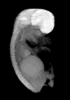

Carnegie Stage 23 (56 post-ovulatory days)

Most embryos at stage 23 are approximately 56-57 postovulatory days old and measure 23-32 mm in length. Distinguishing criteria for this stage include fusion of the eyelids at the medial and lateral margins, clear distinction of the subdivisions of the upper and lower limbs, the forearms appear at or above the level of the shoulders, the superficial vascular plexus of the head is very close to the vertex, and the external genitalia are well developed but not always sufficiently to distinguish the embryo's sex.

(NOTE: These specimens are late stage 23.)